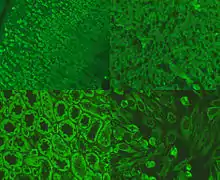

Anti-mitochondrial antibodies (AMA) are autoantibodies, consisting of immunoglobulins formed against mitochondria,[1] primarily the mitochondria in cells of the liver.

The presence of AMA in the blood or serum of a person may be indicative of the presence of, or the potential to develop, the autoimmune disease primary biliary cirrhosis (PBC; also known as primary biliary cholangitis). PBC causes scarring of liver tissue, confined primarily to the bile duct drainage system. AMA is present in about 95% of cases.[2] PBC is seen primarily in middle-aged women, and in those afflicted with other autoimmune diseases.